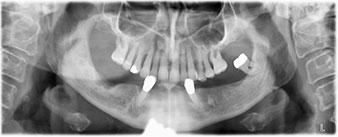

La paziente, 64 anni, presenta una dentatura residua di denti 38, 33 e 43 e una protesi combinata innestata nella mandibola (Fig. 1 e 2).